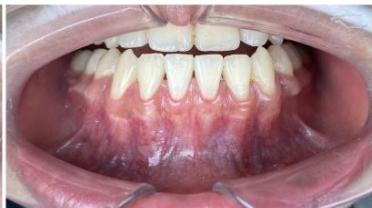

### b) Intraoral Examination

Intraoral examination revealed severe proclination and protrusion of both the maxillary and mandibular incisors [6]. The occlusal relationship was Class I at the canine (tooth 3) and first molar (tooth 6) levels bilaterally. A critical unfavorable biological factor was the proximity of the mandibular incisor roots to the labial cortical plate, representing a high-risk condition when planning extraction-based anterior retraction mechanics [10-12]. All four third molars were present.

Figure 2: Pre-Treatment Intraoral Photographs